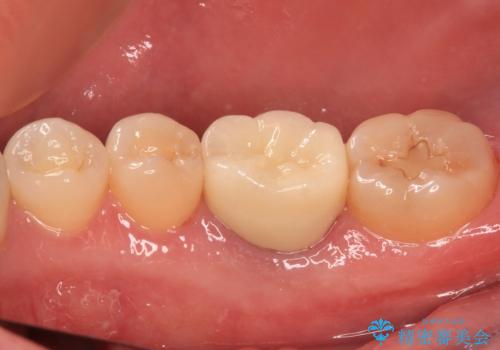

腫れていた歯茎は根管治療後に解消され、適合の良いセラミッククラウンを装着することができました。